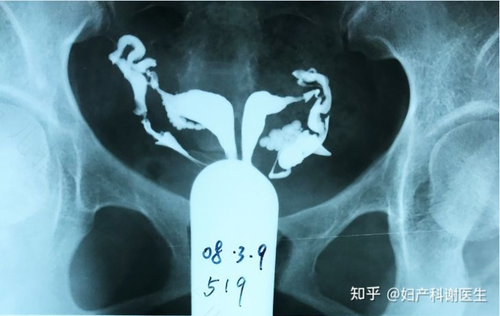

很多女性在不不孕不育的时候,都需要进行子宫造影检查,这就可以了解子宫腔、盆腔以及输卵管的情况。如果输卵管有堵塞的现象,便可以通过造影清晰的显现出来。那么,女性朋友做子宫造影需要注意什么呢?